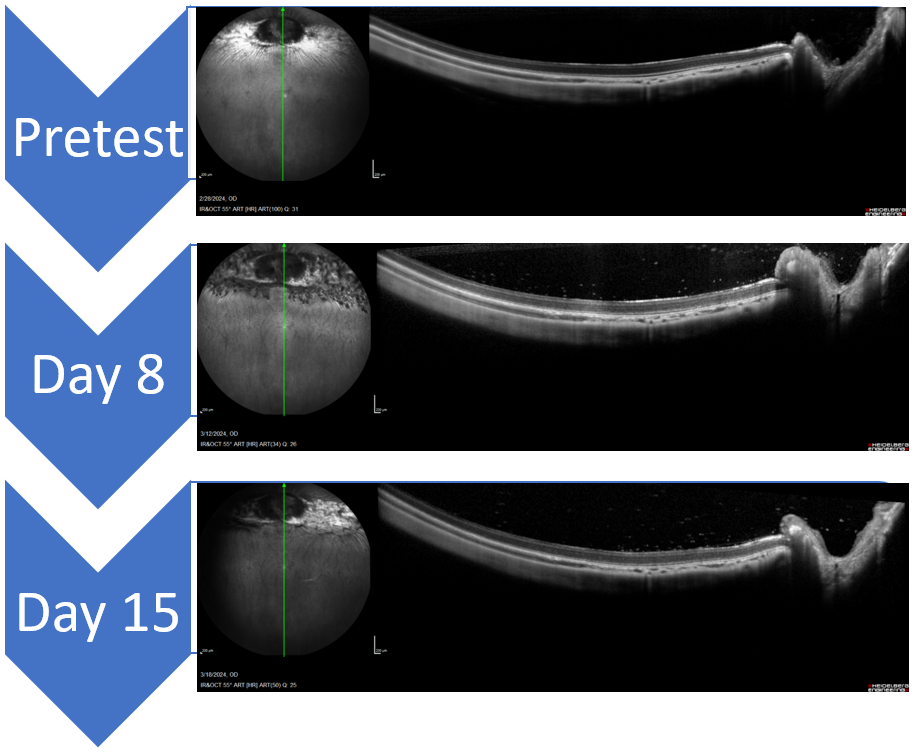

• Optical Coherence Tomography (OCT) – OCT imaging allows for longitudinal cross-section scans of the retina to be collected. In addition to being able to measure changes related to angiogenesis, this technique allows for the assessment of the inflammatory response induced by the VEGF injection and the effect that potential therapeutic candidates have on this response.